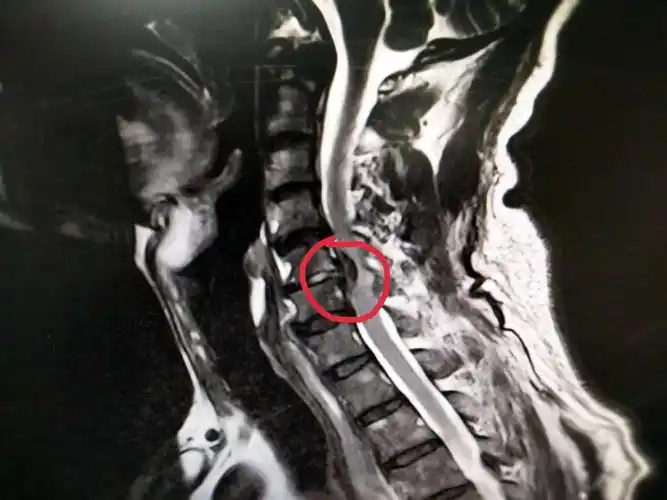

周三待术?脊髓型颈椎病

颈椎核磁共振显示颈5-6椎间盘突出,压迫神经,致相应平面椎管

脊髓型颈椎病的病例

脊髓型颈椎病

一例脊髓性颈椎病